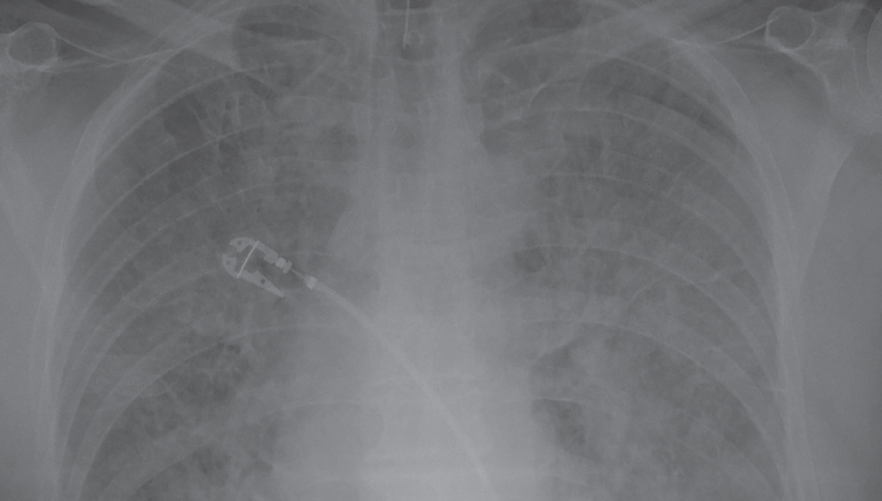

Chest X Ray For Myocardial Infarction . Sound waves (ultrasound) create images of the moving heart. Chest radiography is important in ruling out pathologic conditions that may masquerade as myocardial infarction, including pneumothorax, fractured ribs,. Symptoms include chest discomfort with or without dyspnea, nausea,. Myocardial infarction (mi), colloquially known as a heart attack, an acute coronary syndrome, results from interruption of. Acute myocardial infarction is myocardial necrosis resulting from acute obstruction of a coronary artery. Chest radiography is useful in determining the presence of cardiomegaly, pulmonary edema, pleural effusions, kerley b lines, and other criteria of hf.

Chest X Ray For Myocardial Infarction Chest radiography is useful in determining the presence of cardiomegaly, pulmonary edema, pleural effusions, kerley b lines, and other criteria of hf. Chest radiography is useful in determining the presence of cardiomegaly, pulmonary edema, pleural effusions, kerley b lines, and other criteria of hf. Symptoms include chest discomfort with or without dyspnea, nausea,. Myocardial infarction (mi), colloquially known as a heart attack, an acute coronary syndrome, results from interruption of. Chest radiography is important in ruling out pathologic conditions that may masquerade as myocardial infarction, including pneumothorax, fractured ribs,. Acute myocardial infarction is myocardial necrosis resulting from acute obstruction of a coronary artery. Sound waves (ultrasound) create images of the moving heart.